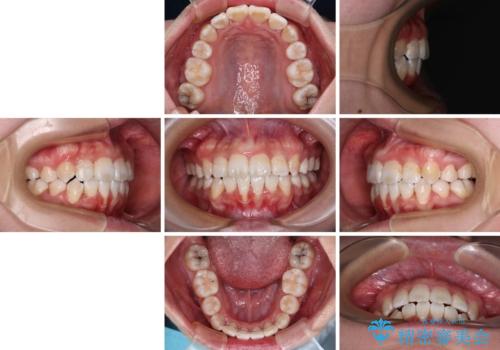

下顎前歯の歯肉が元々薄く、歯肉退縮リスクがあったため、細心の注意を払って治療を進めましたが、残念ながら1歯退縮を起こして歯根が露出してしまいました。

今後、患者様と相談しながら、歯肉移植を行っていく予定です。